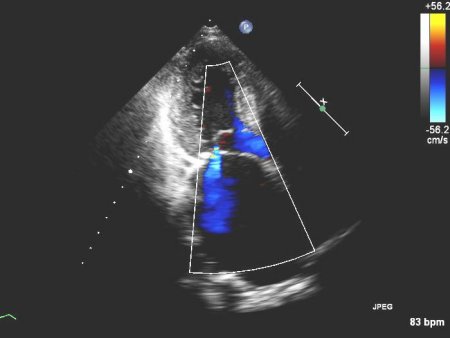

Mitral regurgitation

Apical 4-chamber view of 1-2+ posteriorly directed mitral regurgitation

From the collection of Samir Kapadia and Mehdi H. Shishehbor